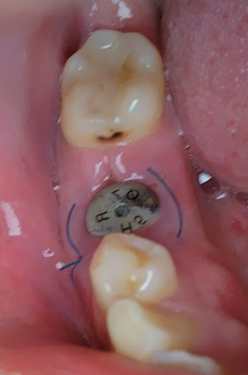

수술 13일 차 사진입니다. 벌어졌던 수술부위가 잘 아물었습니다. 오늘 이후로 부드러운 칫솔로 양치를 해볼까 합니다. 오늘은 실밥 제거와 사진상에 보이는 충치를 치료했습니다. 이가 빠지기 전에는 보이지 않아서 몰랐던 부분의 충치입니다. 생각보다 많이 썩어있었습니다. 별생각 없이 치료하러 갔는데 오늘도 마취주사를 맞았습니다. 마취주사는 정말 적응하기 힘든 거 같습니다. 마취하고 충치 치료하고 본뜨고 대략 한 시간 정도 걸렸습니다. 약 10일 후에 인레이를 씌우면 충치 치료는 끝이 납니다.

치료 후의 사진입니다. 실밥이 제거되니 무척이나 후련합니다. 충치도 사라지니 기분도 좋아졌습니다. 치과 치료를 받을 때마다 이빨 관리를 정말 잘해야겠다고 다짐하지만 세월이 흐르면 또 충치가 생겨버립니다. 이빨 관리 은근히 힘든 거 같습니다.